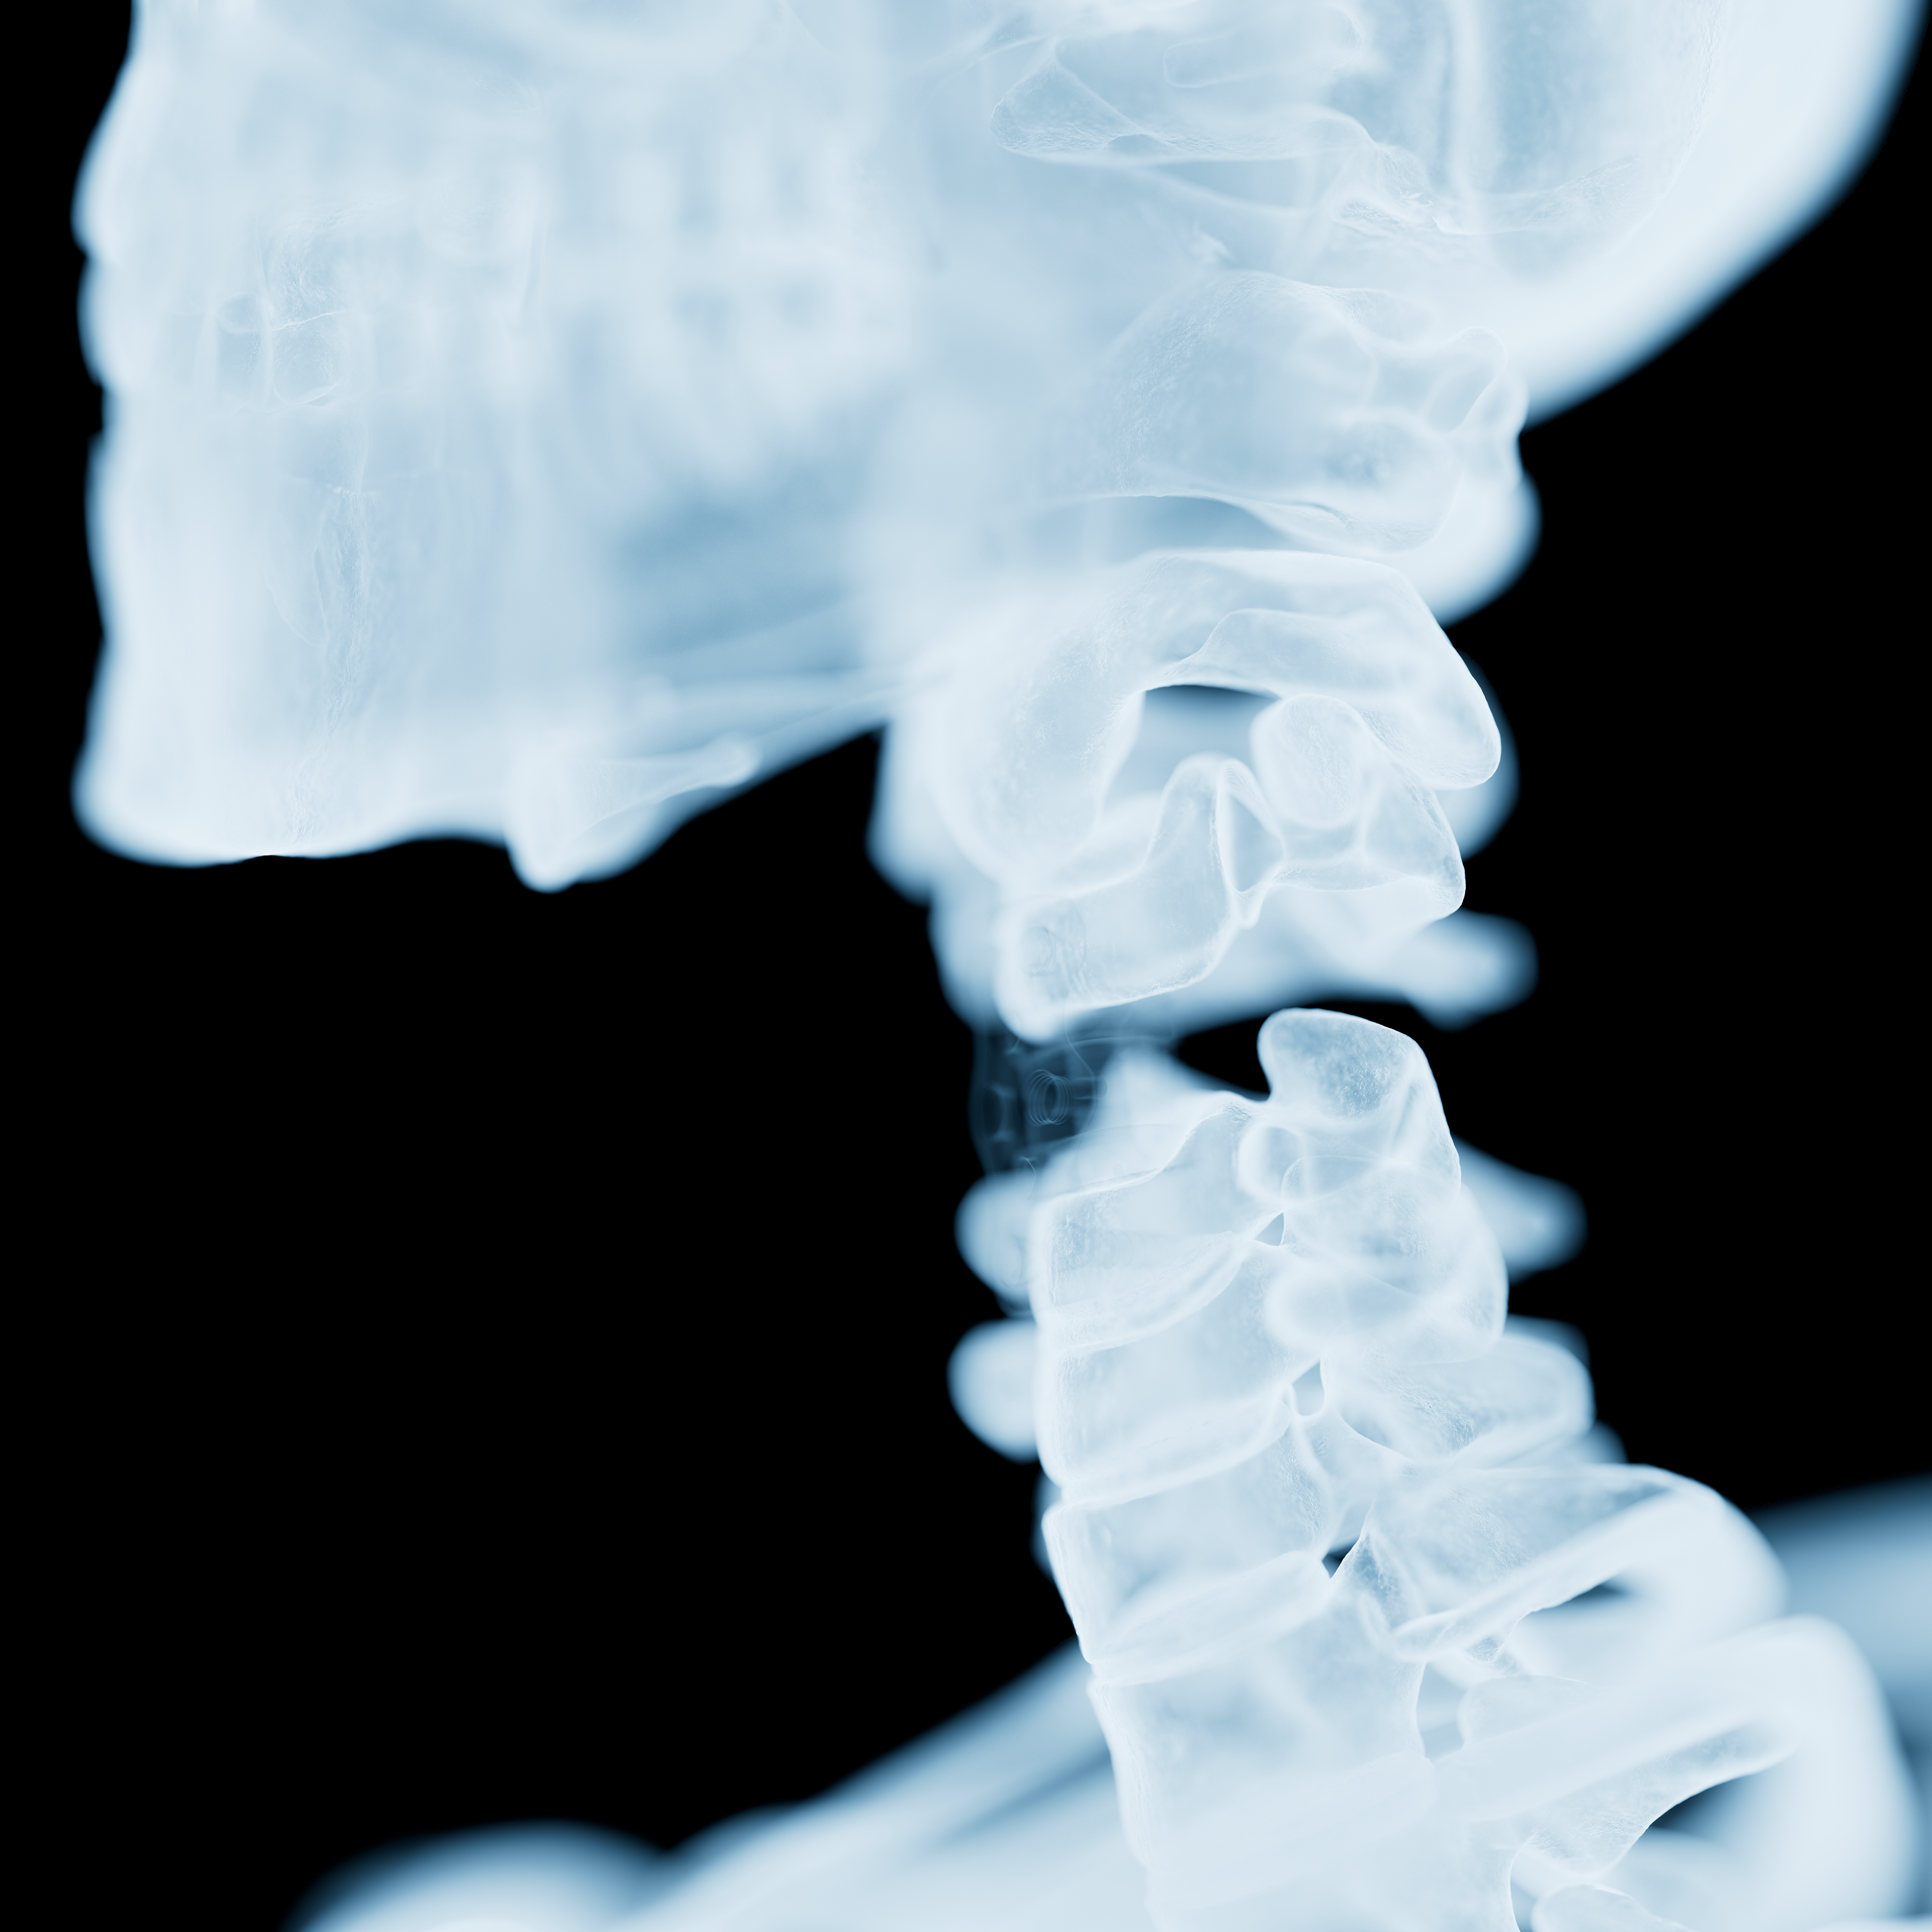

Ein grosser Vorteil von "Black Armor" ist seine Durchlässigkeit für Röntgenstrahlen, was die Nachbehandlung und Bildgebung im vergleich zu herkömmlichen metlllischen Implantaten stark vereinfacht. Um dies zu veranschaulichen, sind folgende Bilder entstanden.